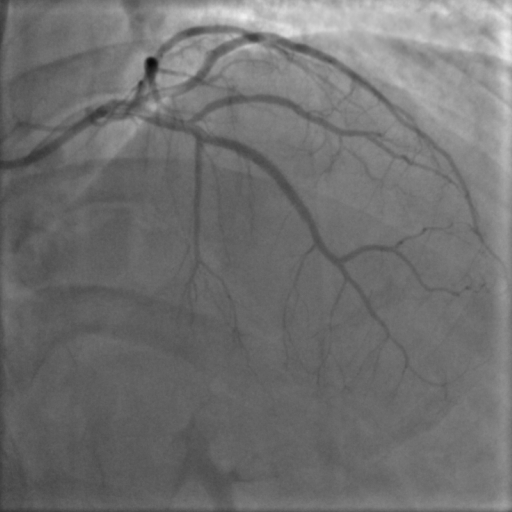

PCI was planned to LAD ISR lesion through right radial approach with 6 French sheath. Optical Coherence Tomography (OCT) was chosen for intracoronary imaging modality as it gives high resolution images to know the plaque morphology, exact mechanism of ISR which help in planning device selection and also to assess the adequacy of lesion preparation. 3.5 EBU 6 French Guiding catheter was taken with Runthrough (Terumo ,Japan) guidewire. Initial OCT ( Dragonfly OpStar catheter, Abbott,USA) run was done. Thick neointimal hyperplasia was seen with neoatheroma in mid portion of ISR lesion. mm as mean diameter in the distal reference segment was 2.9 mm (EEL to EEL) and the measured stent diameter was 2.6 mm. The MLA at the tightest point was 1.15 mm2 . Lesion length was 28 mm. We planned to do plaque modification with cutting balloon and correction of stent under expansion with non compliant balloon followed by drug coated balloon application.Initial plaque modification was done with wolverine (Boston Scientific,USA) 2.5 X 10 mm cutting balloon up to 12 atm from distal to proximal followed by 3.0 x12 mm NC Quantum Apex (Boston Scientific,USA) balloon inflation from 16 to 20 atm. Final OCT run was done which showed intimal micro tears with good lumen gain. 3x 30 mm Agent (Boston Scientific,USA) Drug-Coated Balloon was inflated within the lesion area at 6 atm nominal pressure for 90 seconds. TIMI 3 flow was seen with good vessel expansion on angiography.

Case Summary